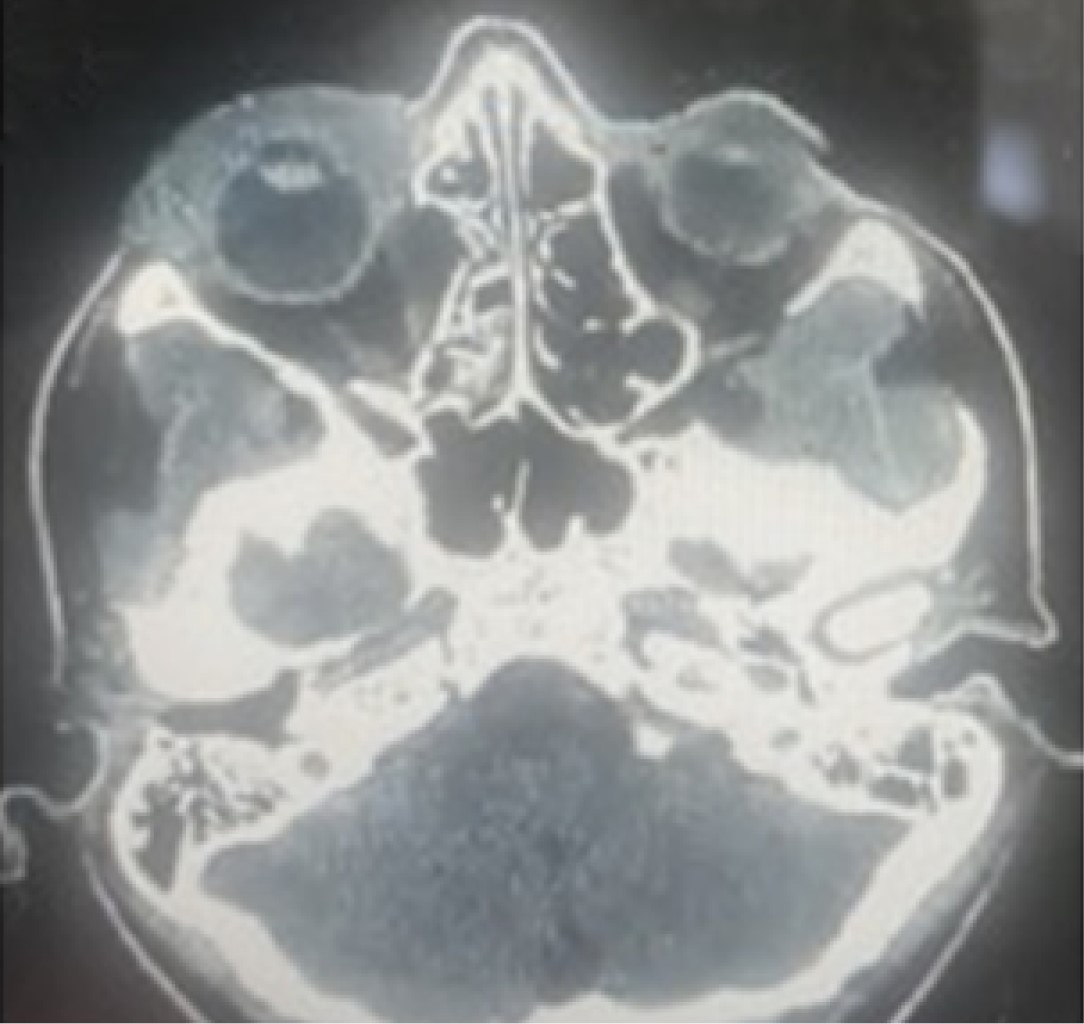

Paciente femenino de 35 años, víctima de un traumatismo de alta energía (patada de caballo), atendida por el equipo de Cirugía Oral y Maxilofacial y Traumatología de UNIMED Birugui. Presentaba un traumatismo en la región orbitaria derecha, que evolucionaba con signos clínicos de enoftalmia, distopía, hiposfagia y oftalmoplejía en lateralidad y supraversión, asociados a pérdida de agudeza visual.

La tomografía computarizada coronal de la cara muestra una extensa destrucción de la pared orbital medial (Figura 5) y la reconstrucción con malla de titanio para corregir el extenso defecto (Figura 6).

Bajo anestesia general, se realizó un acceso bicoronal e infraciliar para la extracción de tejidos blandos y la reducción de la fractura de la pared medial así como la reconstrucción con malla orbital premoldeada, devolviendo el marco y el volumen orbitario. Una tomografía de la cara en el postoperatorio inmediato mostró la reconstrucción de la órbita con malla y tornillo del sistema de fijación de 1.5 mm (Figuras 7 y 8). A continuación, se realizó una prueba de ducción forzada con fórceps Adson y se comprobó la movilidad pasiva del globo. Seguimiento de 60 días en el postoperatorio, sin presentar restricciones de movimiento ocular, distopía y diplopía, con retorno de la agudeza visual, y edema discreto en región periorbitaria.